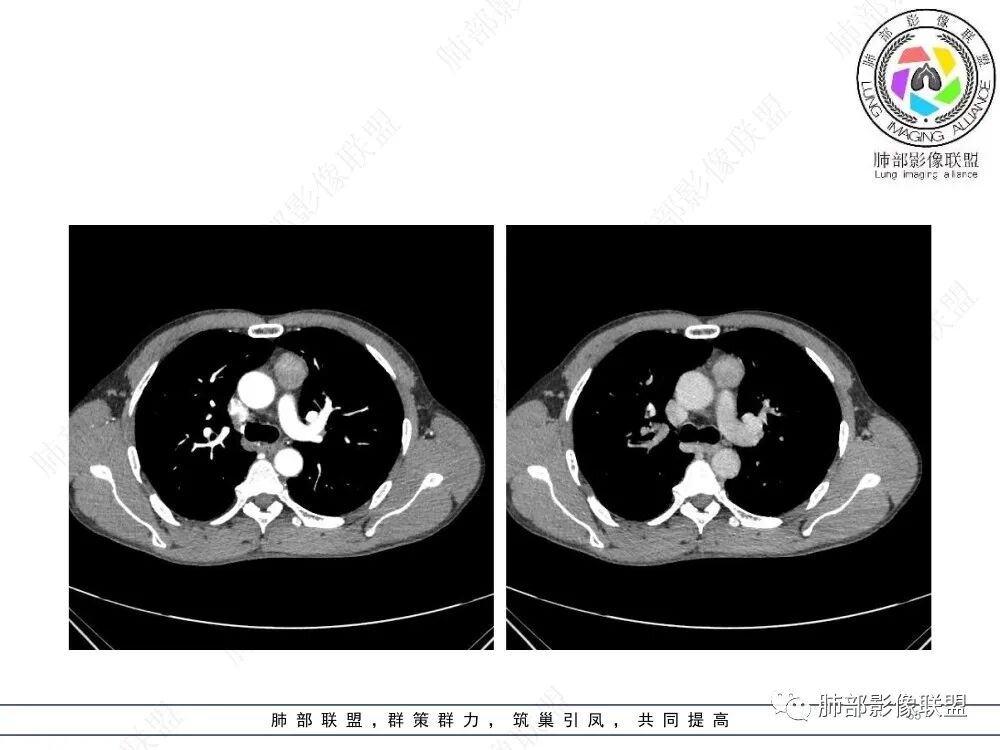

放射小白:男性47岁,前纵隔团块状占位,边界尚清,增强中度强化,内部疑似纤维分隔,常规考虑胸腺瘤可能(A/AB型),鉴别类癌、CD。

瑞欣:中年男性,检验未见明显异常,前纵隔软组织快影,边界清,可见明显强化,首先考虑胸腺瘤,鉴别淋巴瘤,畸胎瘤,生殖细胞瘤。

金豆:晨读:定位前纵隔,膨胀性生长,质地中等,边界清,有浅分叶,中等强化,似乎有裂隙低密度,常规胸腺瘤(B1)。

Yishion:晨读:纵隔占位,偏侧生长,边界清楚,有浅分叶,强化明显,其内似见纤维分隔,常规考虑胸腺瘤(AB型)。

蓝天白云:晨读:47岁男,前纵隔占位,边界清,有浅分叶,中等强化,胸腺瘤(B1)。

宇宙:前纵膈偏左类圆形肿块,边界清晰光整,与大血管脂肪间隙清,密度均匀,轻中度强化,考虑胸腺瘤,A型?鉴别胸腺癌。

玫:男,47岁,咳嗽,咳痰一年,前纵隔软组织密度肿块影,边界清晰,内密度均匀,增强扫描轻度强化,考虑胸腺瘤可能。

周太狼:中年男性,前上纵隔胸腺区软组织团块占位,边界清,增强中度强化,内密度较均匀,常规考虑胸腺瘤。

月亮圆了!:前纵隔包块,边界清,有分叶,密度不均,中等强化,考虑胸腺瘤。

衡妈🇨🇳:中年男性,前纵隔偏左侧实性占位,密度相对均匀,边缘分叶,周围脂肪结构略模糊,增强后动脉期不均匀强化,有低密度区,纤维分隔显示不清。考虑胸腺瘤B1 B2型。

朱伟超:中年男性,前纵膈偏离中线肿块,浅分叶,内有分隔,中等不均匀强化,常规胸腺瘤。

流心明智:男,47,咳嗽、咳痰1年余。胸部CT:前纵膈偏左类圆形肿块,瘤肺界面清晰光整,纵隔侧部分层面絮状影?平扫密度较均匀,增强后轻度强化,内可见宽带及线样低密度分隔。邻近左上肺受压凹陷。考虑胸腺肿瘤,AB型?胸腺Ca?鉴别淋巴瘤、N源性肿瘤、CD等。

2、影像特点:前纵隔偏左侧软组织影,密度相对均匀,未见明显包膜钙化及实质内钙化,局部边缘浅分叶,周围脂肪间隙密度增高、浑浊,未见侵犯大血管、未见纵隔内淋巴结转移、未见侵犯心包内结构、未见胸膜转移结节、未见肿块沿着纵隔胸膜蔓延,未见胸腔积液。增强后动脉期不均匀强化,未见明显纤维分隔。